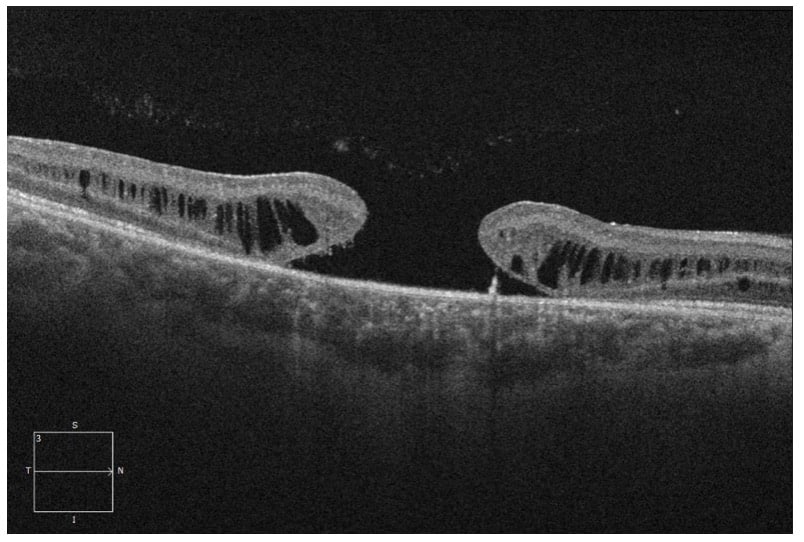

A 25-year-old male was referred for a second opinion of progressively worsening vision OU for the past 14 years. His ocular history was significant for previous diagnosis of macular hole OU as a child. The Fundus exam revealed bilateral large macular holes with yellow/brown pigmentation OU (figure 1). OCT (Optical Coherence Tomography) confirmed the full thickness macular holes with foveal retinoschisis OU (figure 2). Given the history of pediatric bilateral macular holes in absence of trauma, Electroretinogram (ERG) was performed, which showed decreased B-waves (negative ERG) in both eyes (figure 3), consistent with X-linked retinoschisis.